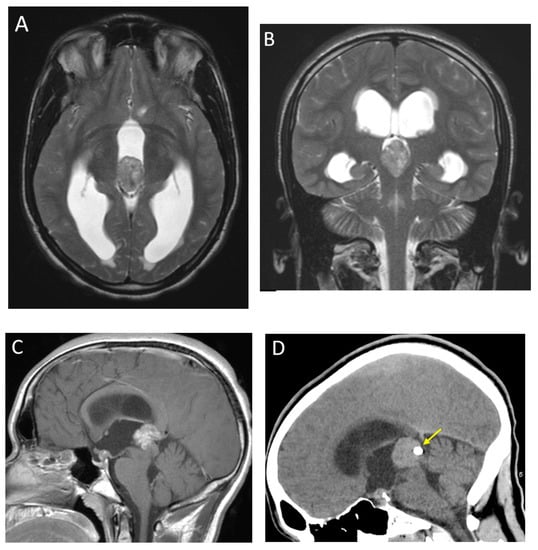

| Pilocytic astrocytoma | Cerebellum (most common), brainstem, optic chiasm/hypothalamus | Most commonly, cyst with enhancing mural nodule although cystic component can be variable, and may be completely solid |

| Ganglioglioma | Temporal lobe | Variable, although commonly cystic with enhancing mural nodule No diffusion restriction |

| Dysembryoplastic neuroepithelial tumor (DNET) | Frontal or temporal lobes, cortically based | Well-circumscribed, triangular configuration, ‘bubbly’ appearance Absent or minimal enhancement May be associated with cortical dysplasia Scalloping of the overlying calvarium |